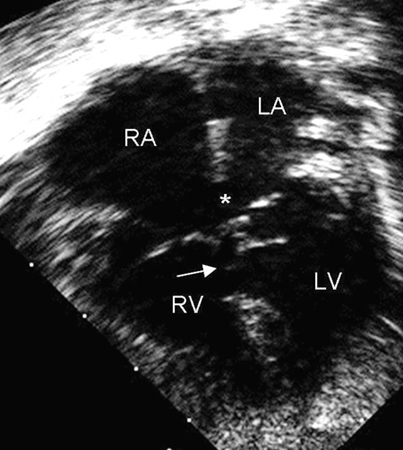

Imagem da ecografia apical de 4 câmaras de um defeito do septo atrioventricular (DSAV) completo. Note o ostium primum no defeito do septo atrial (DSA) (*) e o defeito do septo ventricular (DSV) de entrada adjacente (seta). (AD) átrio direito; (AE) átrio esquerdo; (VD) ventrículo direito; (VE) ventrículo esquerdo

Imagem cedida por Patrick W. O'Leary, MD